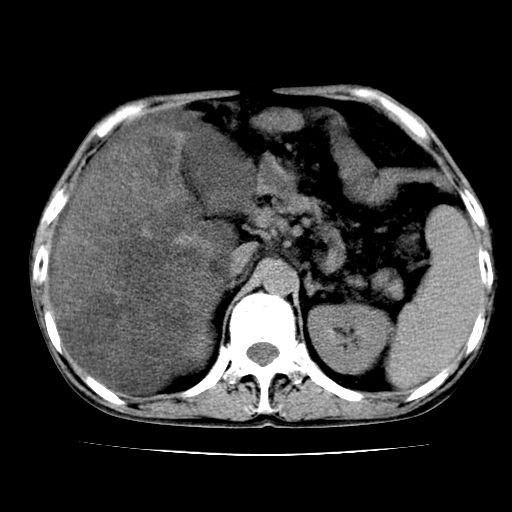

男,55岁,发现“肝硬化”5年,现腰疼、腹胀10余日,巩膜黄染、腹稍胀,肝肋下3指,质硬无压疼,移动性+,血生化:总胆、直胆、间胆均升高。

g1:肝硬化、脾大、腹水。

2:脂肪肝。

3:弥漫性肝癌待排。

肝硬化,脾大,腹水

脂肪肝

肝内多发低密度灶(建议增强扫描除外肝癌)